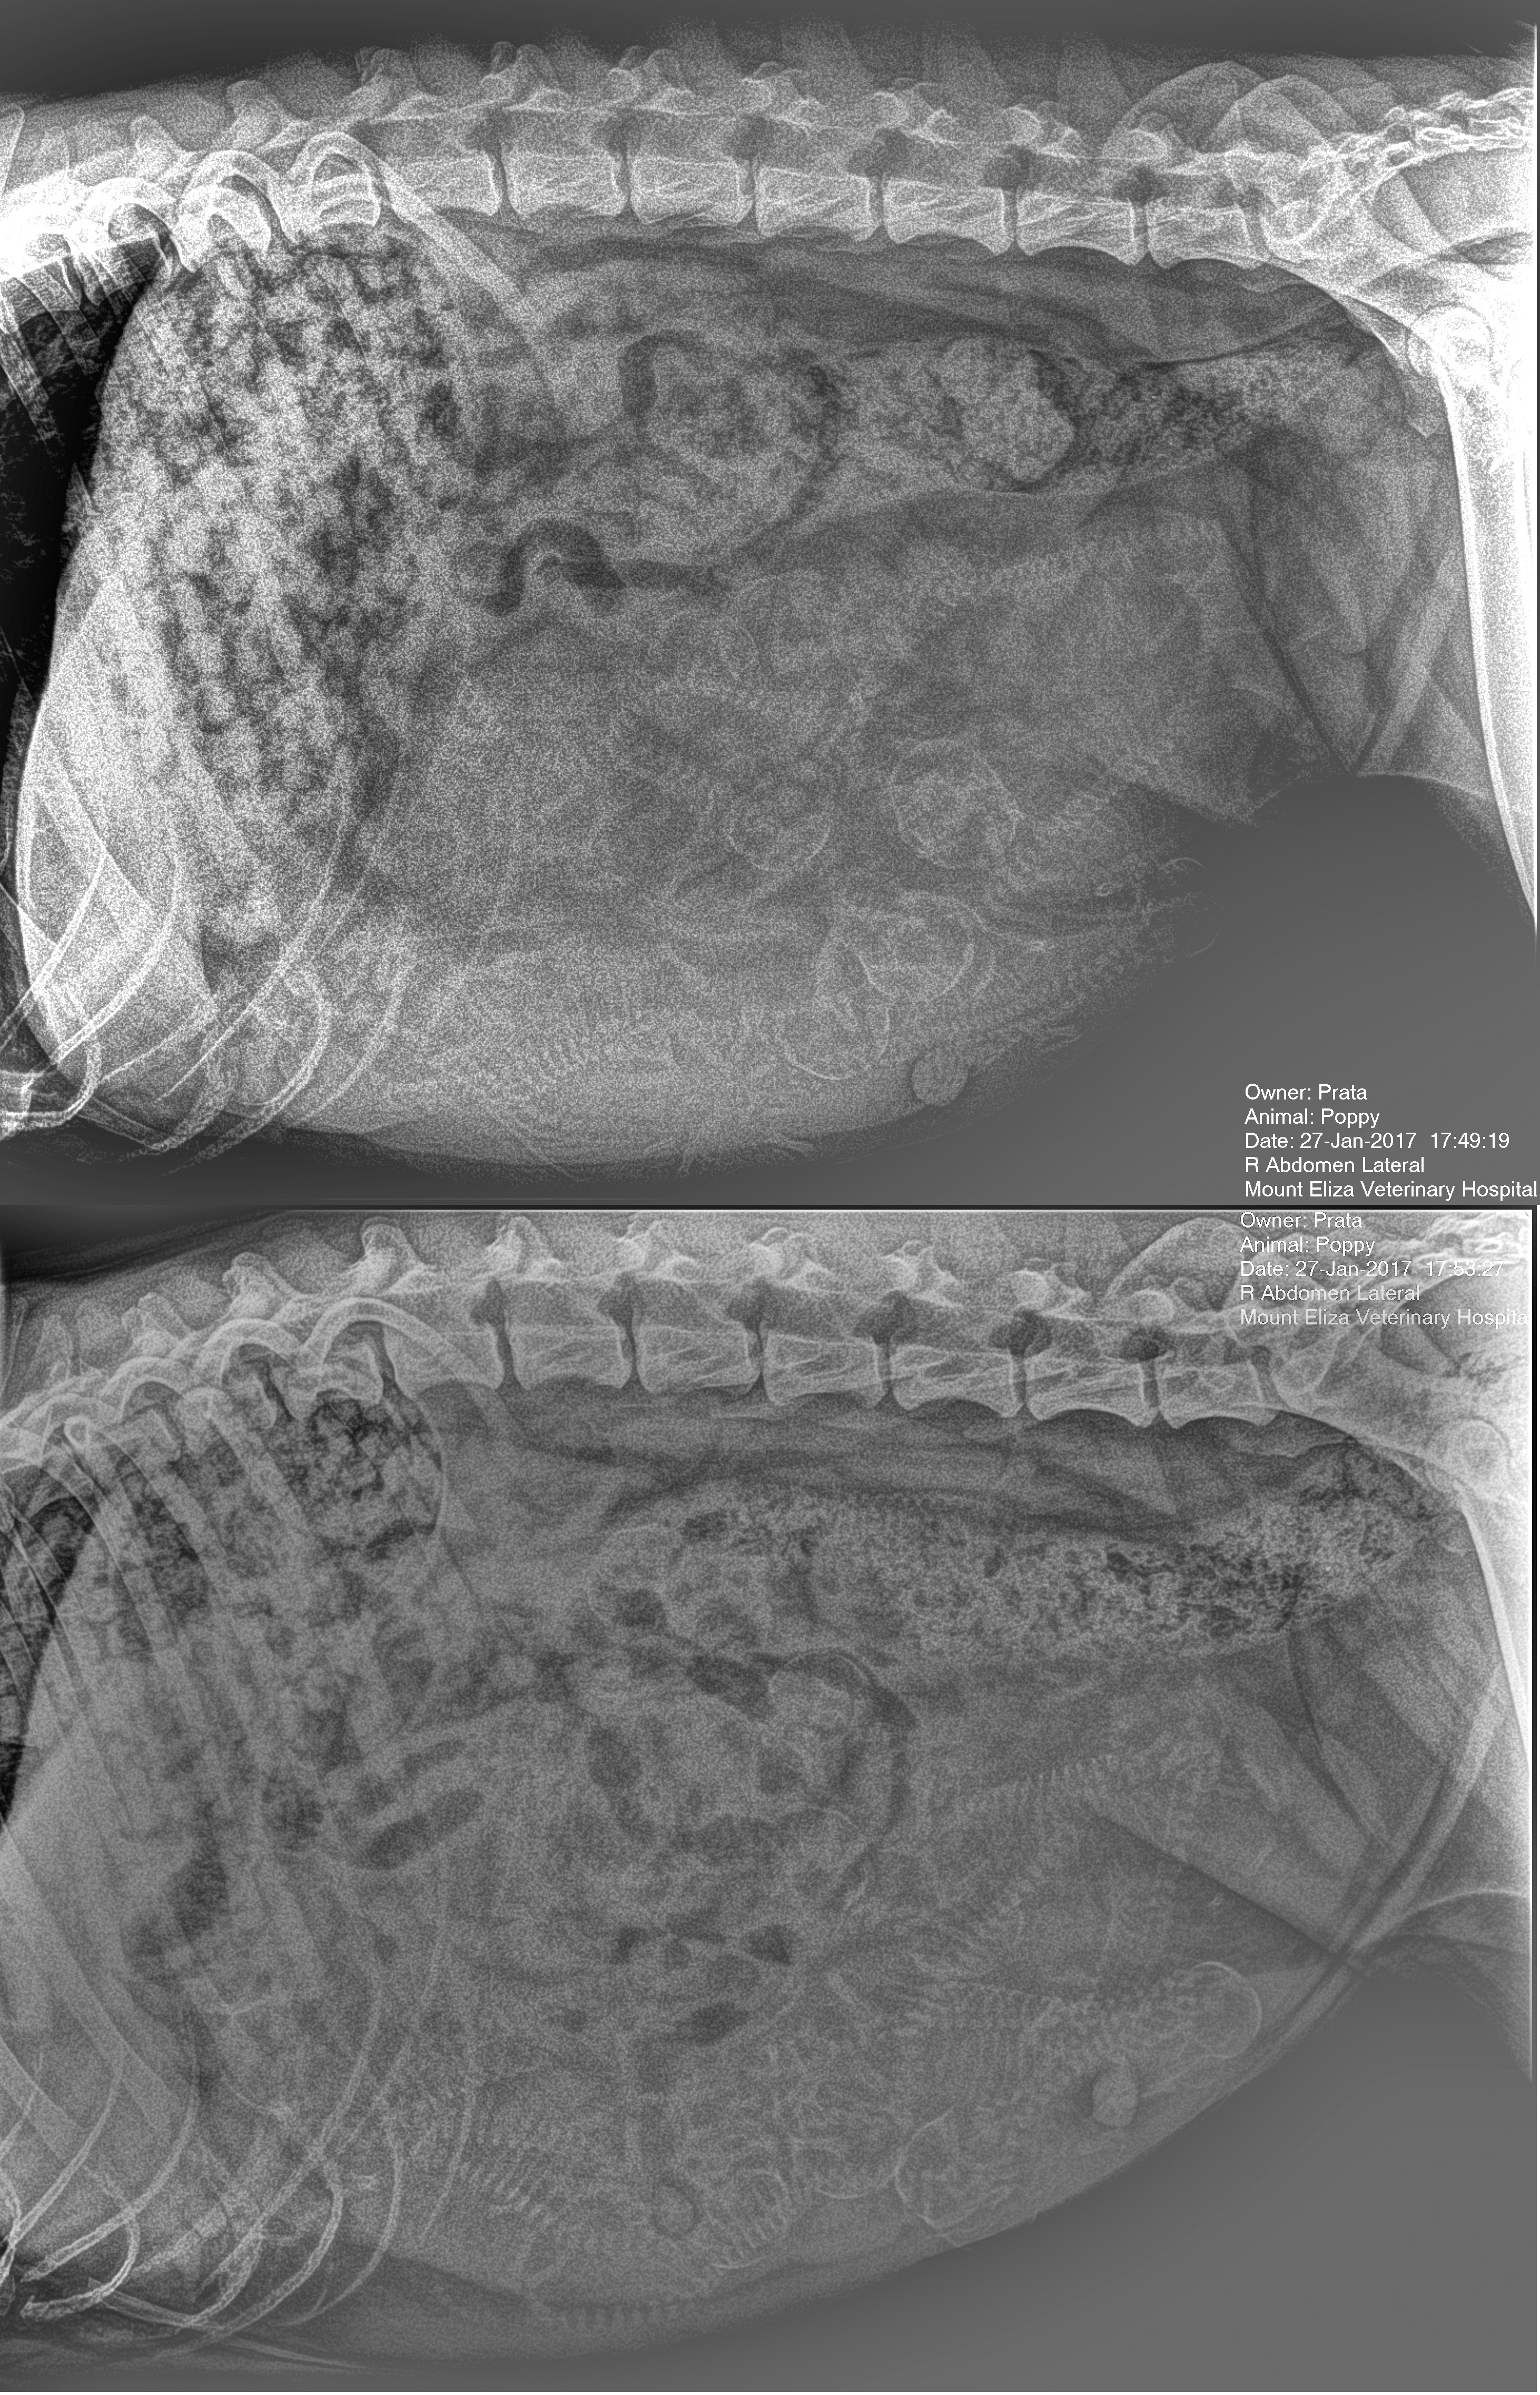

Day 50: At the vet today Poppy weighed in at a portly 34.6kg! We went to discuss worming and availability of after hours vet services once she goes into labour. We were also there to get an X-ray to do a puppy count. Results were difficult to be certain but various opinions estimated 9-10+. It is possible to see both skulls and spines on the X-ray below. How many do  you think?

poppy_puppies_full-size

Two X-rays taken at the vet from both sides.